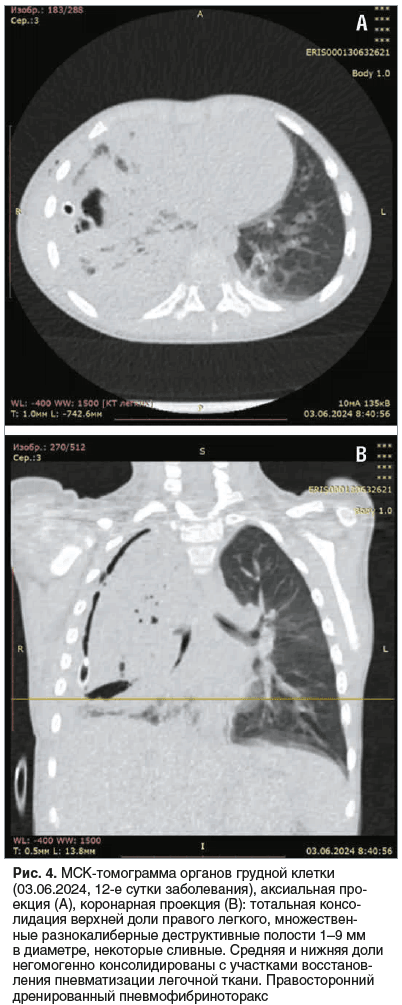

30.05.2024 (8-е сутки заболевания) — при УЗИ ОГП верхняя и средняя доли легкого консолидированы, неструктурны, с чередованием участков понижения и повышения эхогенности без четких контуров. Воздух прослеживается только в проекции корня легкого. Сосудистый рисунок резко обеднен. Констатированы массивные некротические изменения верхней и средней долей правого легкого (рис. 3). 31.05.2024 (9-е сутки заболевания) — мальчик в стабильно тяжелом состоянии переведен в отделение торакальной хирургии, где было продолжено проведение дренирования плевральной полости, санационные бронхоскопии. К 03.06.2024 (12-е сутки заболевания) по данным УЗИ ОГП на фоне безвоздушной ткани правого легкого в задних отделах появились множественные неправильной формы включения газа — дренированные зоны некроза легочной паренхимы. В передневерхней части легкого трансбронхиальное дренирование участков некроза отсутствовало. Справа визуализировались эхопризнаки пневмофибриноторакса. В этот период состояние ребенка оставалось тяжелым, начинающееся дренирование очагов деструкции сопровождалось подъемом температуры до 39,5 °С, повторным повышением уровней лейкоцитов (25,97×109/л), СРБ (236,91 мг/л), D-димера (10 799 нг/мл). Кроме того, отмечалось увеличение уровня ЛДГ (430,3 Ед/л при норме 110–295 Ед/л) как маркера повреждения тканей. В то же время уровень ПКТ продолжал снижаться (1,04 нг/мл). При МСКТ определялась тотальная консолидация верхней доли правого легкого, сегментарные бронхи прослеживались фрагментарно, визуализировались разнокалиберные воздушные полости от 1 до 9 мм, некоторые из них были сливными. Отмечена негомогенная консолидация средней и нижних долей. В средней доле выявлена полость с пенистым содержимым 29×31×9 мм, сообщающаяся с плевральной полостью (рис. 4).